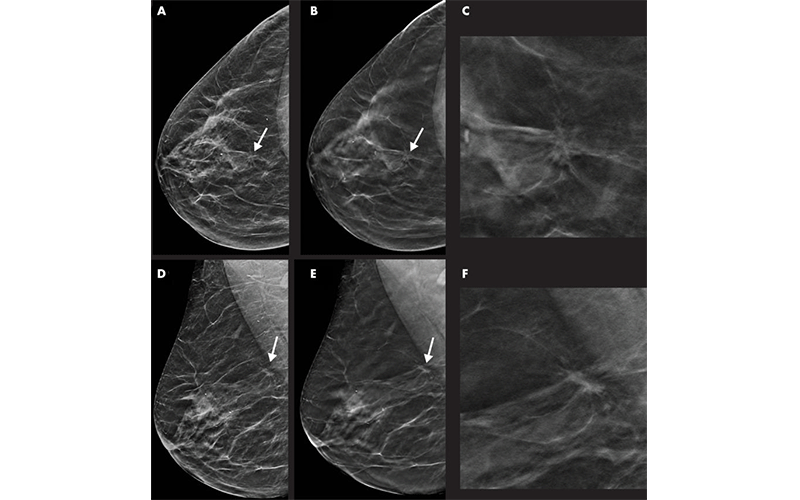

Digital breast tomosynthesis (DBT), in combination with synthetic mammography, improves cancer detection over digital mammography alone, according to a study from Italy published in Radiology.

DBT Detects Higher Proportion of Early-Stage Cancers

DBT at the first round and at rescreening detected a higher proportion of early-stage cancers than screening with digital mammography.

The cancer detection rate was 8.1 per 1,000 for rescreening with DBT and synthetic mammography compared with 4.5 per 1,000 for rescreening with mammography. There was no difference in the recall rate at rescreening with both DBT and synthetic mammography and mammography.

At rescreening, the proportion of tumors stage-II or above was 14.5% with DBT and synthetic mammography, considerably higher than the 8.5% rate with mammography.

“The lower number of stage II or above cancers with the DBT plus synthetic mammography screening test demonstrates that DBT has the capability of anticipating the detection of cancers that might become advanced in the following two years,” Dr. Caumo said. “This gives a higher benefit to our patients.”